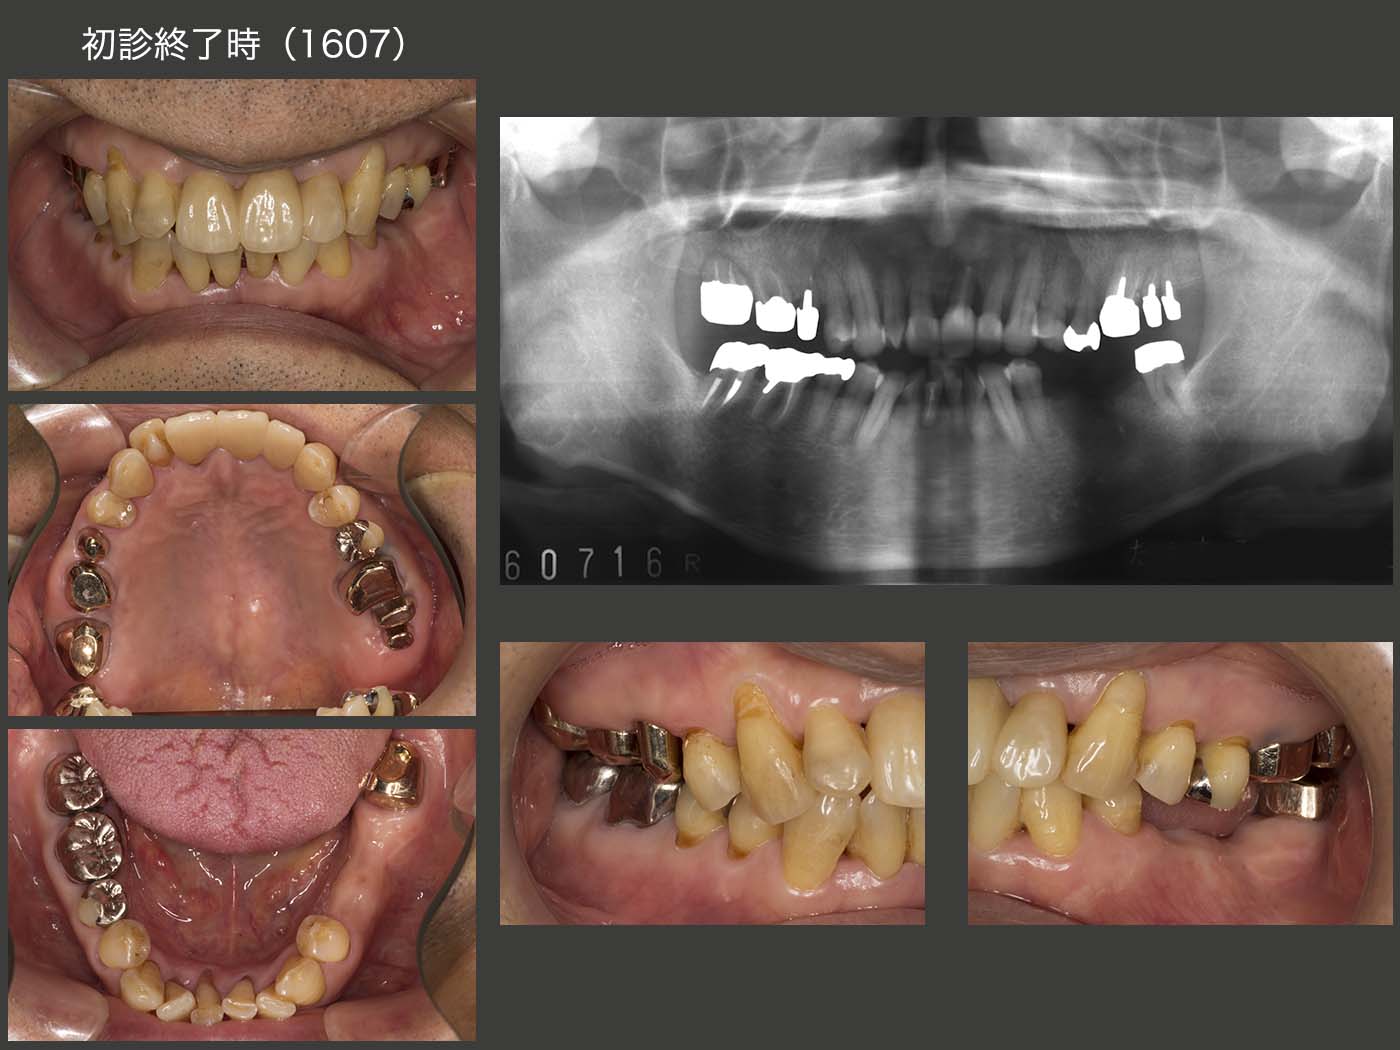

2016年7月,初診終了時の状態.右上7(移植歯)の歯周ポケットは最大5mmの値を示した.左上1は初診時より最大9mmの歯周ポケットがみられたが,歯周基本治療以外,特に治療を施していない.その他の残存歯に問題はみられなかった.なお,初診終了時の残存歯の分布から右側が習慣性咀嚼側になることが予想できる.